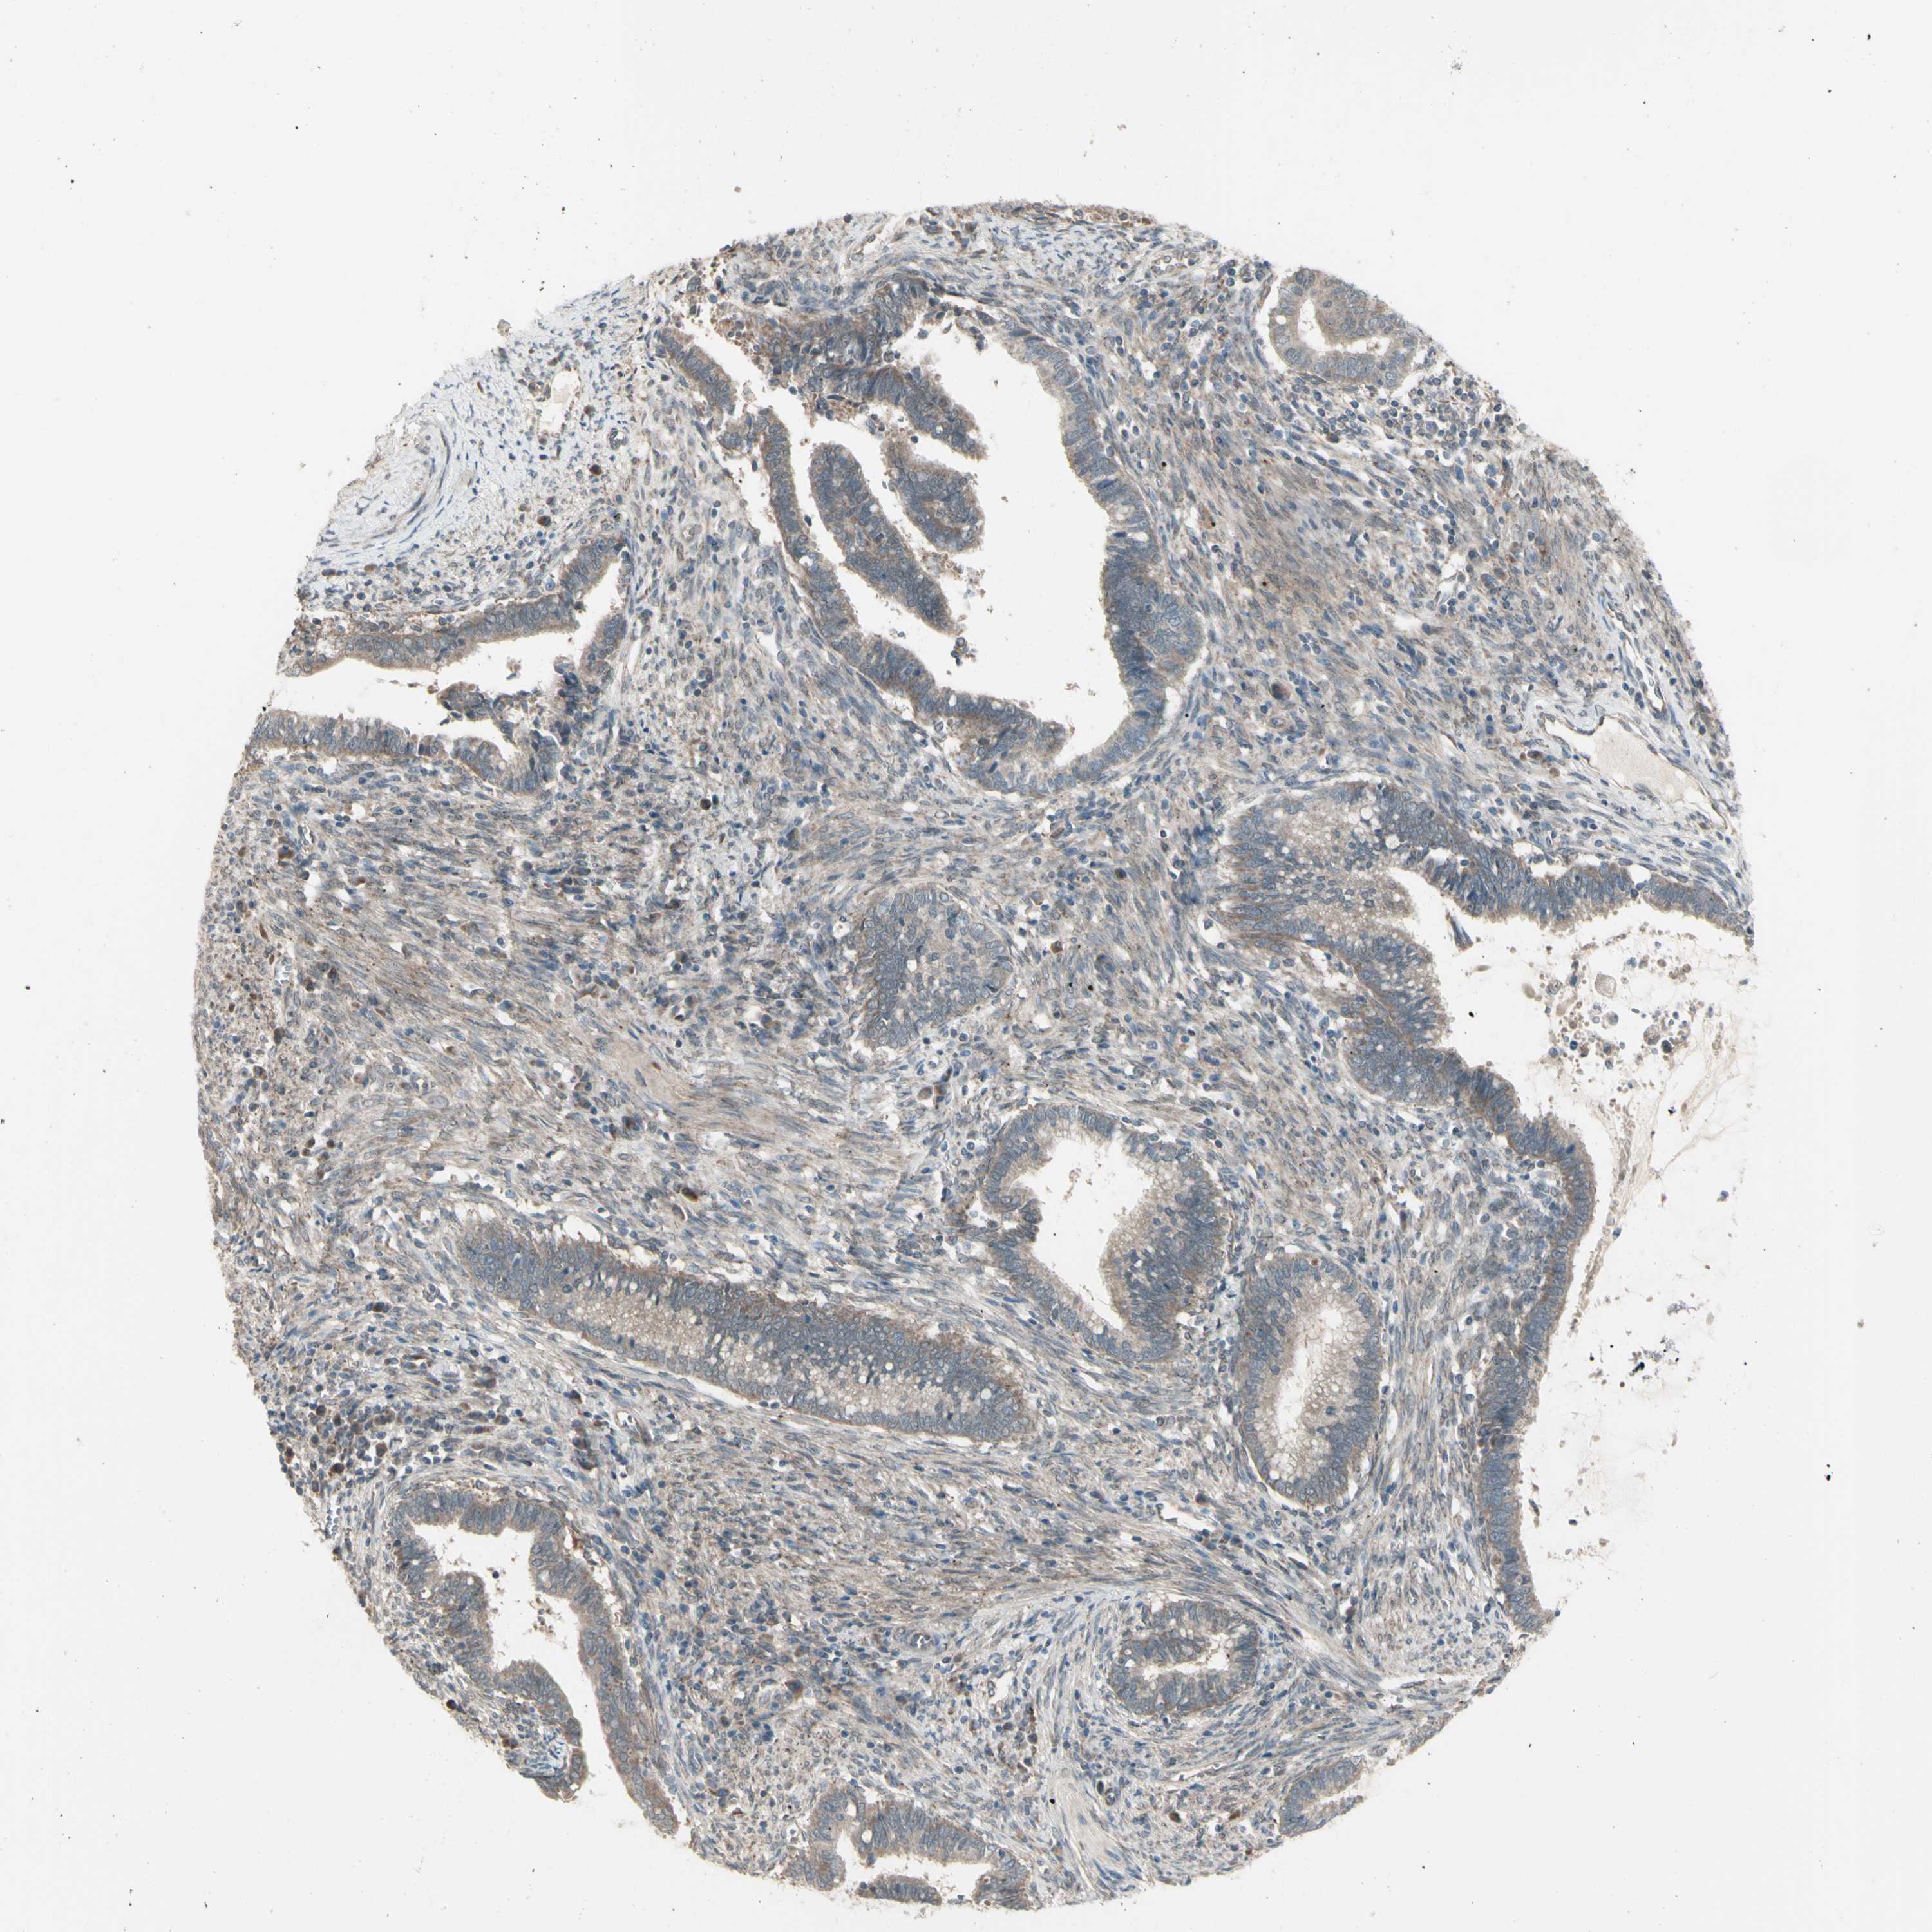

CERVICAL CANCER - Protein expressioni

A mouse-over function shows sample information and annotation data. Click on an image to view it in a full screen mode. Samples can be filtered based on level of antibody staining by selecting one or several of the following categories: high, medium, low and not detected. The assay and annotation is described here.

Note that samples used for immunohistochemistry by the Human Protein Atlas do not correspond to samples in the TCGA dataset.

Antibody stainingi

Antibody staining in the annotated cell types in the current human tissue is reported as not detected, low, medium, or high, based on conventional immunohistochemistry profiling in selected tissues. This score is based on the combination of the staining intensity and fraction of stained cells.

Each image is clickable and will lead to virtual microscopy that enables deeper exploration of all samples and also displays staining intensity scores, fraction scores and subcellular localization as well as patient and tissue information for each sample.

Antibody HPA010551

Staining

High

Medium

Low

Not detected

Intensity

Strong

Moderate

Weak

Negative

Quantity

>75%

75%-25%

<25%

None

Location

Nuclear

Cytoplasmic/membranous

Cytoplasmic/membranous,nuclear

Squamous cell carcinoma, NOS

Adenocarcinoma, NOS